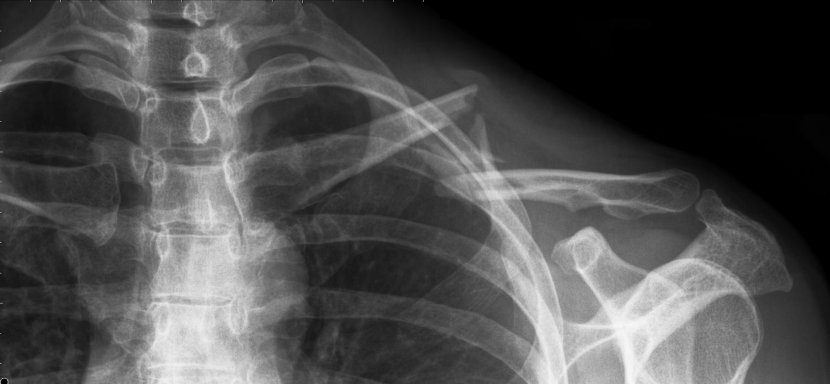

- Broken left collar bone after falling off my bike. (bridge over Adobe Creek on East Bayshore Rd)

The bone was too badly shattered to allow natural healing, so I had a metal plate inserted 10 days after the break, with bone putty to try to guide and speed up bone regeneration. The screws holding the plate backed out and abraded inside of skin, so the same doctor removed the plate after 6 months. The bone broke again 6 days later under light use. A new surgeon worked to fix it by running a threaded rod put down the center of the bone, held in position by a "nut" that sticks out of the back of the shoulder joint. (This is a fairly new procedure and has only been in general use for 1-2 years.) That pin pierced the collarbone and wound up sticking out the front of the bone, threatening to puncture the skin and creating a "teeter-totter" effect for the two halves of my collarbone (preventing rejoining). The surgeon went back again, removed the original pin, and rethreaded a new, longer pin down the back of the two halves of the bone. So far, this seems to be working well (fingers crossed). I will need to go back for more surgery in 12-24 months to have the pin removed.